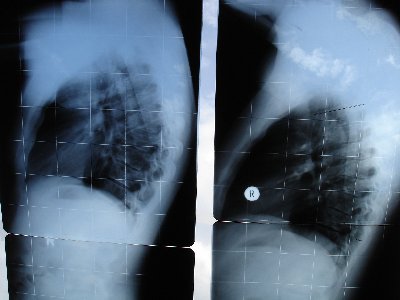

anbei meine Röntgenbilder vorher/nachher. Die Fotos wurden am Fenster gemacht, von daher keine optimale Beleuchtung.

Rechtes Foto: ca. 60 Grad Cobb im Oktober 2004

Linkes Foto: ca. 35 Grad Cobb im August 2005

Für mich als Laien ist der Unterschied nicht so ersichtlich. Aber Dr. Hoffmann war begeistert von dem Fortschritt.

hab nun nochmal die Röbis versucht besser zu fotografieren, besser gehts nicht !

Eure Meinungen interessieren mich sehr, für mich als Laie ist da keine besondere Veränderung erkennbar. Auf dem rechten Bild erkennt man ganz leicht die von Doc Hoffmann eingezeichneten Winkel (rechtes Bild ca. 35 Grad nach Cobb).

Rechtes Bild 35 Grad

Linkes Bild 60 Grad nach Cobb

Das rechte Bild sieht allerdings krummer aus, liegt aber wohl nur an schlechter Röntgung. Bitte auf die WS achten. Auf den ersten Blick wirkt linkes Bild gerader, ist aber laut Doc Hofmann nicht der Fall.

Auch wenn der Bildausschnitt und Haltung etwas ungünstig gewählt ist, die BWS ist eindeutig WESENTLICH gerader und der BWS-Kyphosewinkel eindeutig fast halbiert- Interessant wäre noch die LWS-Lordose und die Beckenkippung zu sehen. Aber Dr. Hoffmann hat mir berichtet, daß die Krankenkassen enormes Sperrfeuer über ihn einschießen, wegen seiner Ganz-WS-Aufnahmen!